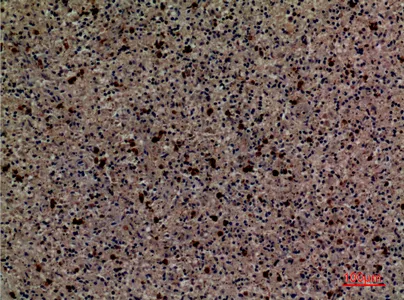

CD13 Rabbit Polyclonal Antibody

Cat: APRab08201

Size1:50μl Price1:$118

Size2:100μl Price2:$220

Size3:500μl Price3:$980

Size2:100μl Price2:$220

Size3:500μl Price3:$980